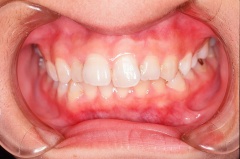

上顎前突

治療前 正面

上顎前歯がかぶっています

治療後 正面

正常になっています